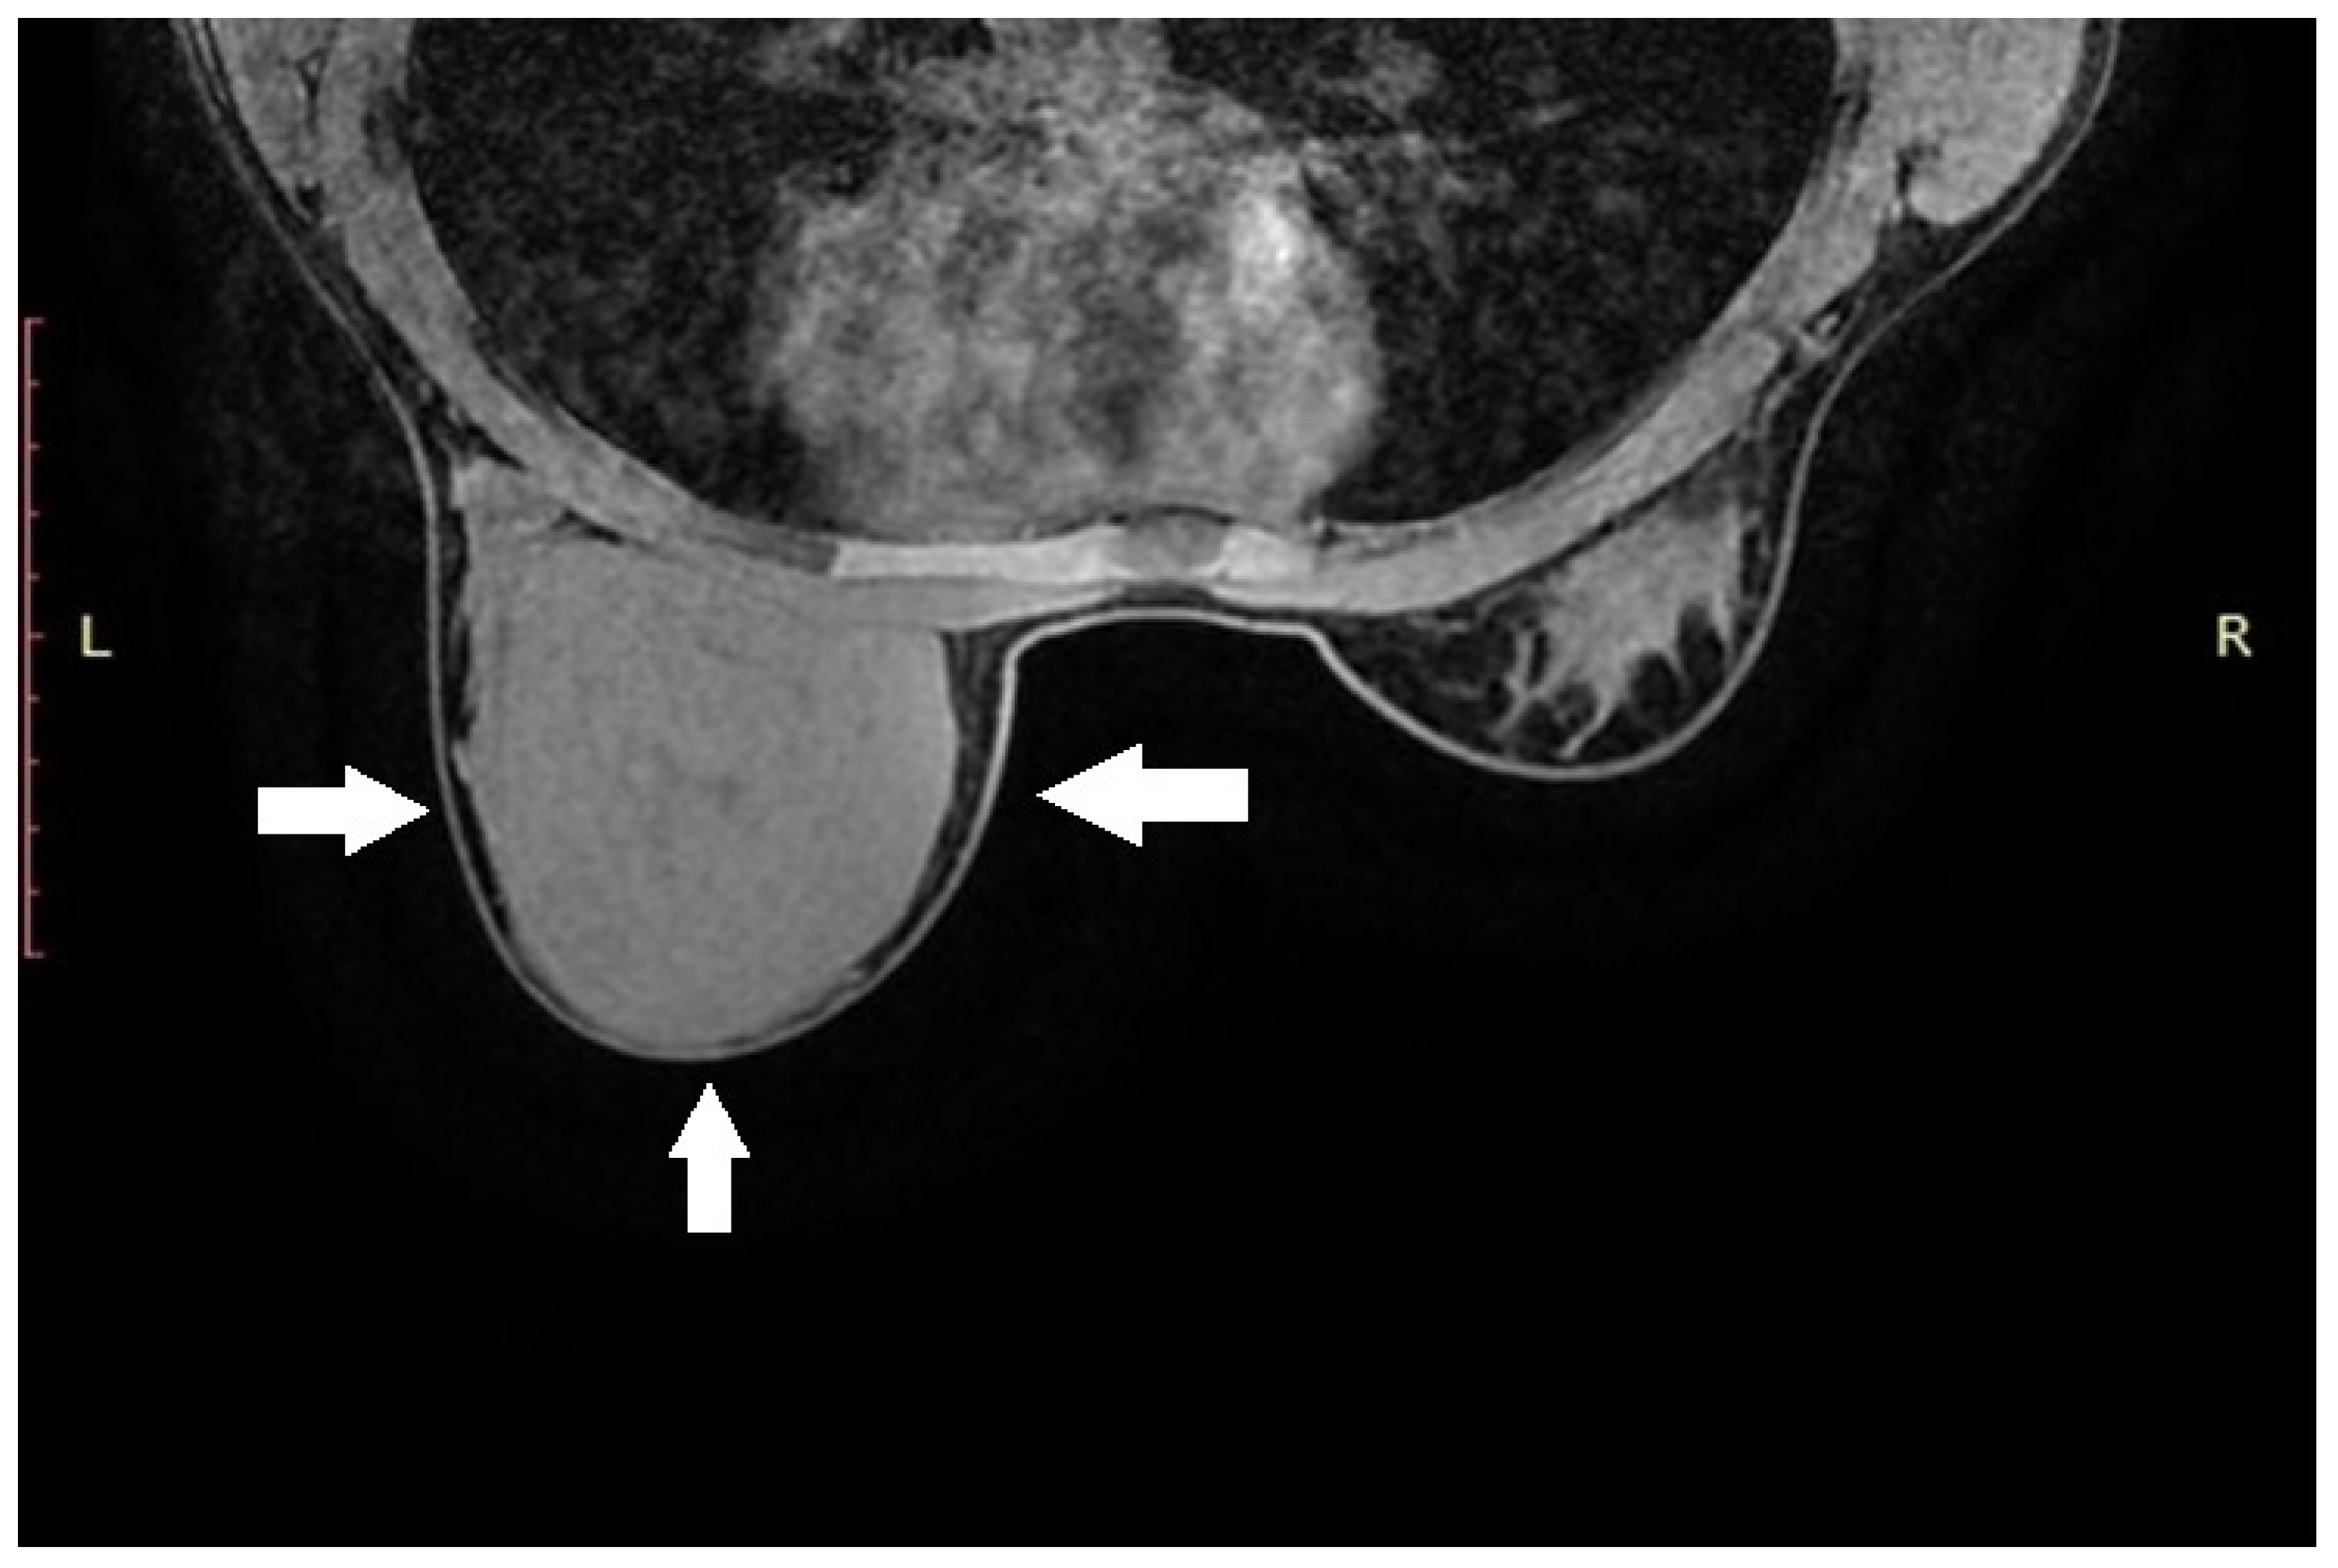

The histopathological examination confirmed the diagnosis of pseudoangiomatous stromal hyperplasia (PASH). The specimen was described as a solid, light gray-to-yellow tumor measuring 11 × 10 × 4.8 cm3, with the capsule preserved and intact (Figure 2 and Figure 3).

On gross examination, PASH typically appears as a well-circumscribed and encapsulated breast lesion, occasionally presenting in a diffuse form. The cut surface is smooth, firm, or rubbery, glistening, and varies in color from gray to tan-pink, yellow, or white [4]. In our patient, the lesion was described as a solid, light gray–yellow mass.

Microscopically, the hallmark of PASH is the presence of slit-like spaces resembling vascular channels, lined by spindle cells, without endothelial markers (CD31–), but with positive CD34 expression, which was also confirmed in our case [4,16].